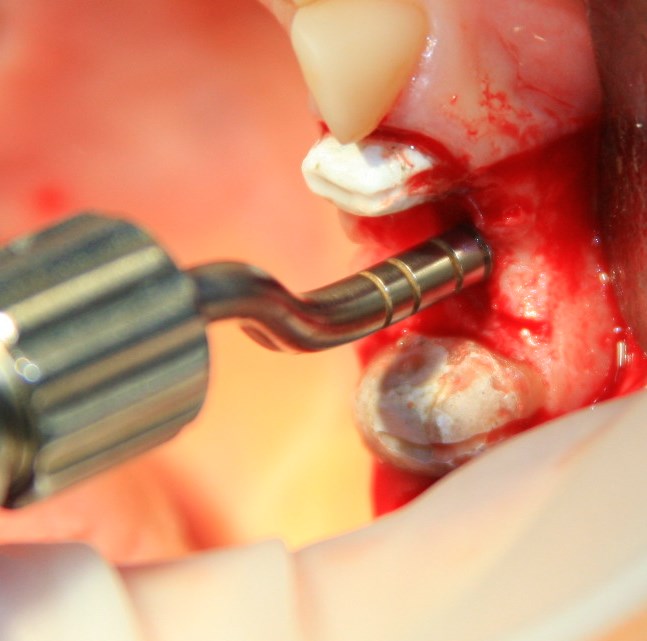

Синуслифтинг: что делать при перфорации слизистой оболочки гайморовой пазухи?